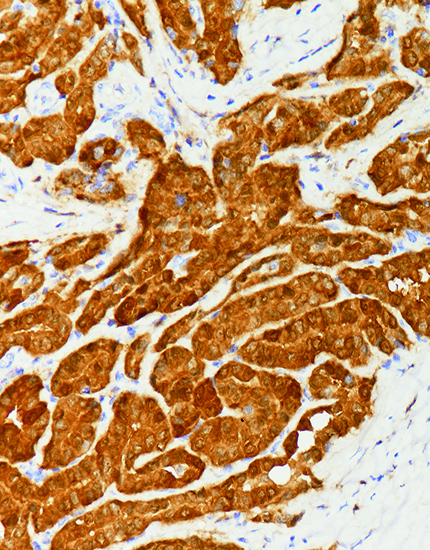

产品名称:HE4

产品编号:MAB-0826

阳性部位:胞质

图片描述:

卵巢浆液性癌,HE4染色,胞质阳性